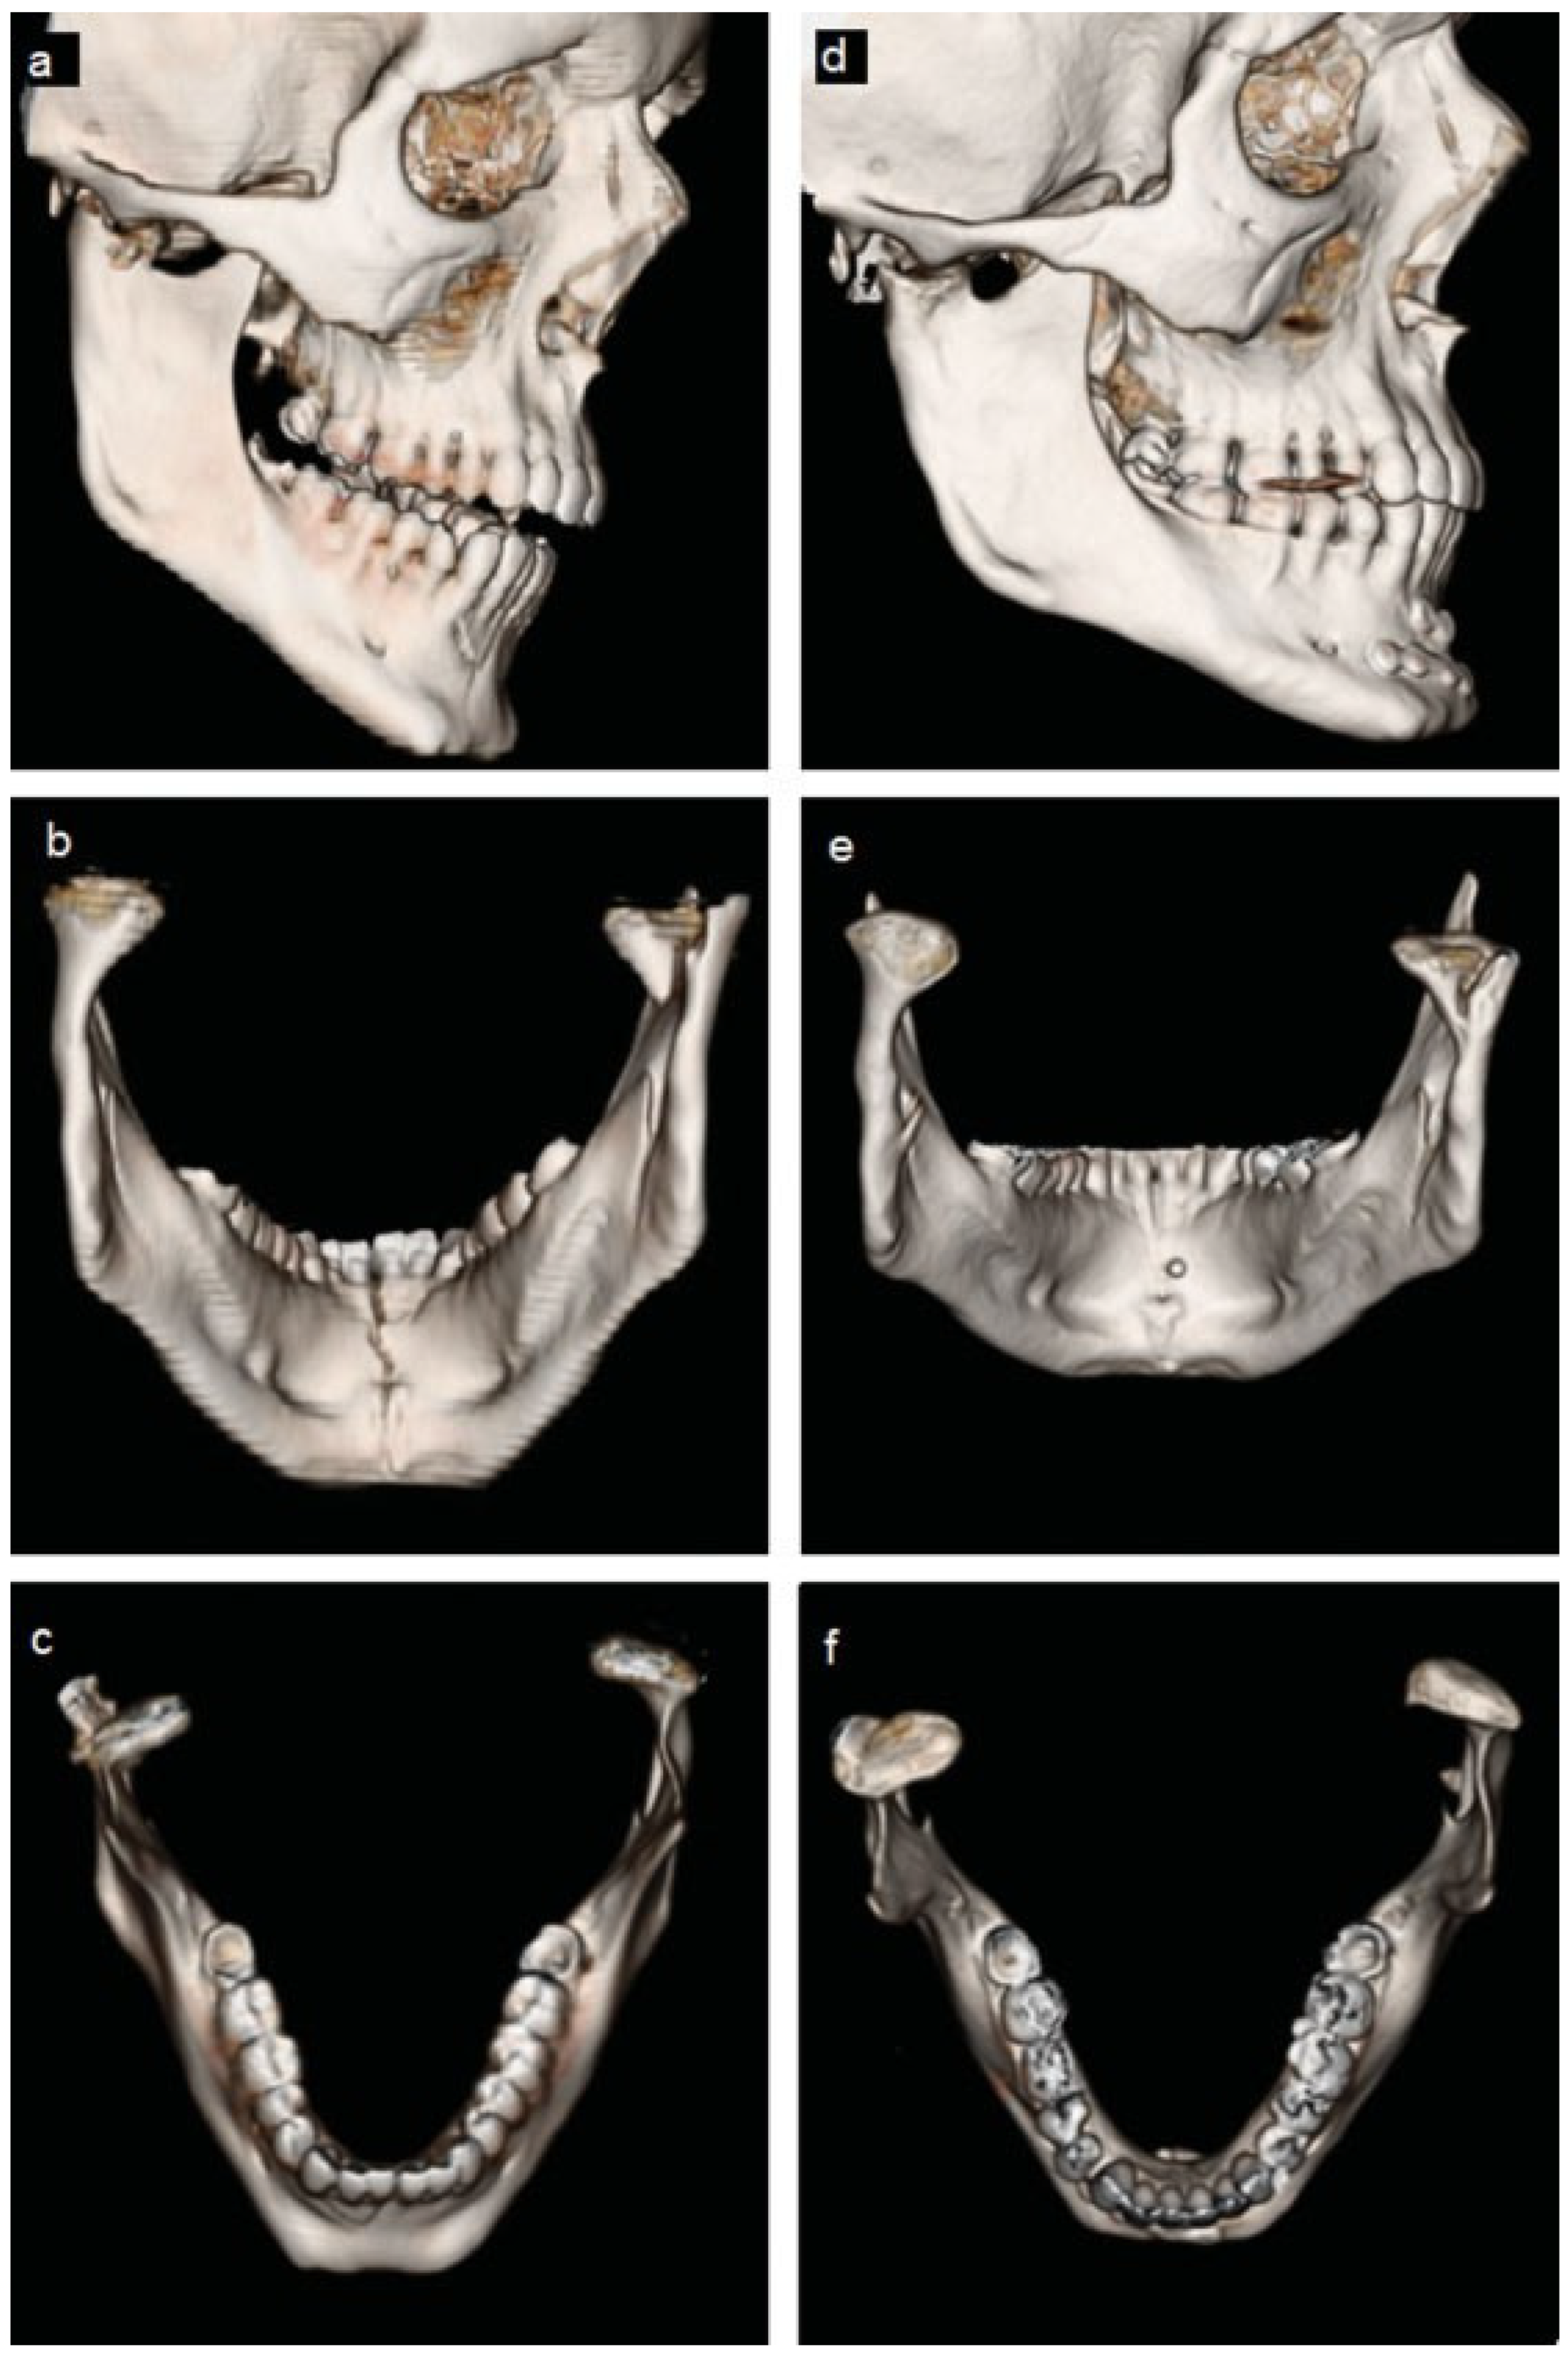

The patient experienced right preauricular pain with jaw movement. An end-to-end unilateral class II malocclusion with a shift of the mandibular midline 2 mm to the left and trismus was documented. CT imaging revealed a displaced, oblique right-sided high subcondylar fracture, and a left nondisplaced parasymphyseal fracture. The fractured right condylar head was displaced anteriorly, medially, and inferiorly (Figure 1a–c and Figure 2a–c). Nonsurgical treatment was instituted, with light intermaxillary elastics on the existing orthodontic appliances with a blenderized diet for 6 weeks. She was compliant with the treatment. During the first 6 weeks of observation the patient was documented to have a stable class I occlusion. She was instructed to continue nocturnal elastics as long as the orthodontist advised and to return to a normal diet as tolerated.

The patient returned in 1 year. At this visit, her only complaint was a sporadic mild dull ache of the right face with prolonged heavy chewing function. She denied joint noise or limitation of motion and tolerated a normal diet. A class I occlusion with excellent intercuspation and excellent mandibular range of motion was documented. There was no myofascial or joint pain with occlusal loading. A CT scan was obtained which showed complete healing of the right condyle which was appropriately positioned in the glenoid fossa (Figure 1d–f and Figure 2d–f). A normal joint space was presented with no evidence of condylar or the glenoid fossa cortical or cancellous osseous abnormalities.

Figure 1. (ac) Comparison between pre-treatment and (df) 1-year posttreatment computed tomography of patient 1. Right-sided, comminuted, medially, and inferiorly displaced high subcondylar fracture is shown in pretreatment images with subsequently well-healed and well-positioned condyle in the posttreatment images. Significant remodeling of the glenoid fossa is seen with downward growth and thickened bone.

Figure 2. (ac) Comparison between pretreatment and (df) 1-year posttreatment 3D reconstructed computed tomography of patient 1. Displacement of the fractured right condyle is visualized again with posttreatment condyle appropriately positioned in the glenoid fossa showing fairly symmetrical shape and appearance and minor irregularities when compared with the left condyle.